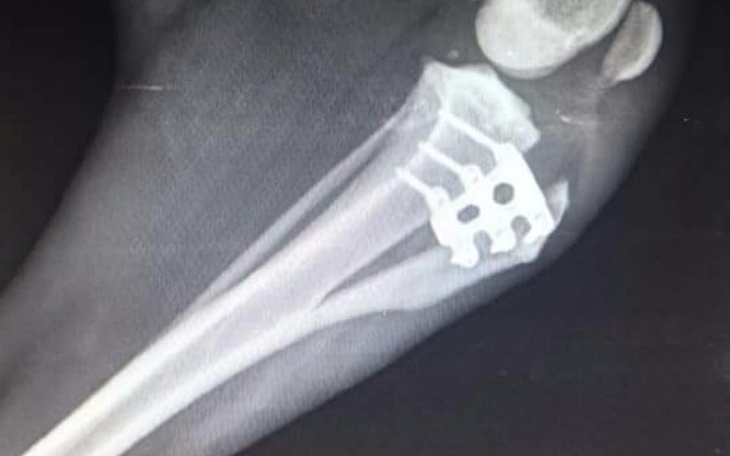

Witam tym razem zbieramy na pokrycie kosztów leczenia naszego podopiecznego Barego. Bary miał przeprowadzony zabieg na wiązadło krzyżowe metodą TTA Rapid, połowę kosztów udało nam się zebrać lecz został jeszcze dług w wysokości 2tyś zł. Z góry dziękujemy za pomoc tą jak i wcześniejsze pozdrawiamy i sami pomagamy :)